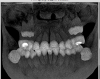

Большой Зеленый Опубликовано 13 марта, 2013 Поделиться Опубликовано 13 марта, 2013 Чтобы получить полезную информацию нужны снимки .Ортопантомограмма,Телерентгенограмма,фотографии моделей челюстей ,фото во рту ... Ссылка на комментарий

Юлианко Опубликовано 13 марта, 2013 Автор Поделиться Опубликовано 13 марта, 2013 Чтобы получить полезную информацию нужны снимки .Ортопантомограмма,Телерентгенограмма,фотографии моделей челюстей ,фото во рту ...Надеюсь это подойдет Ссылка на комментарий